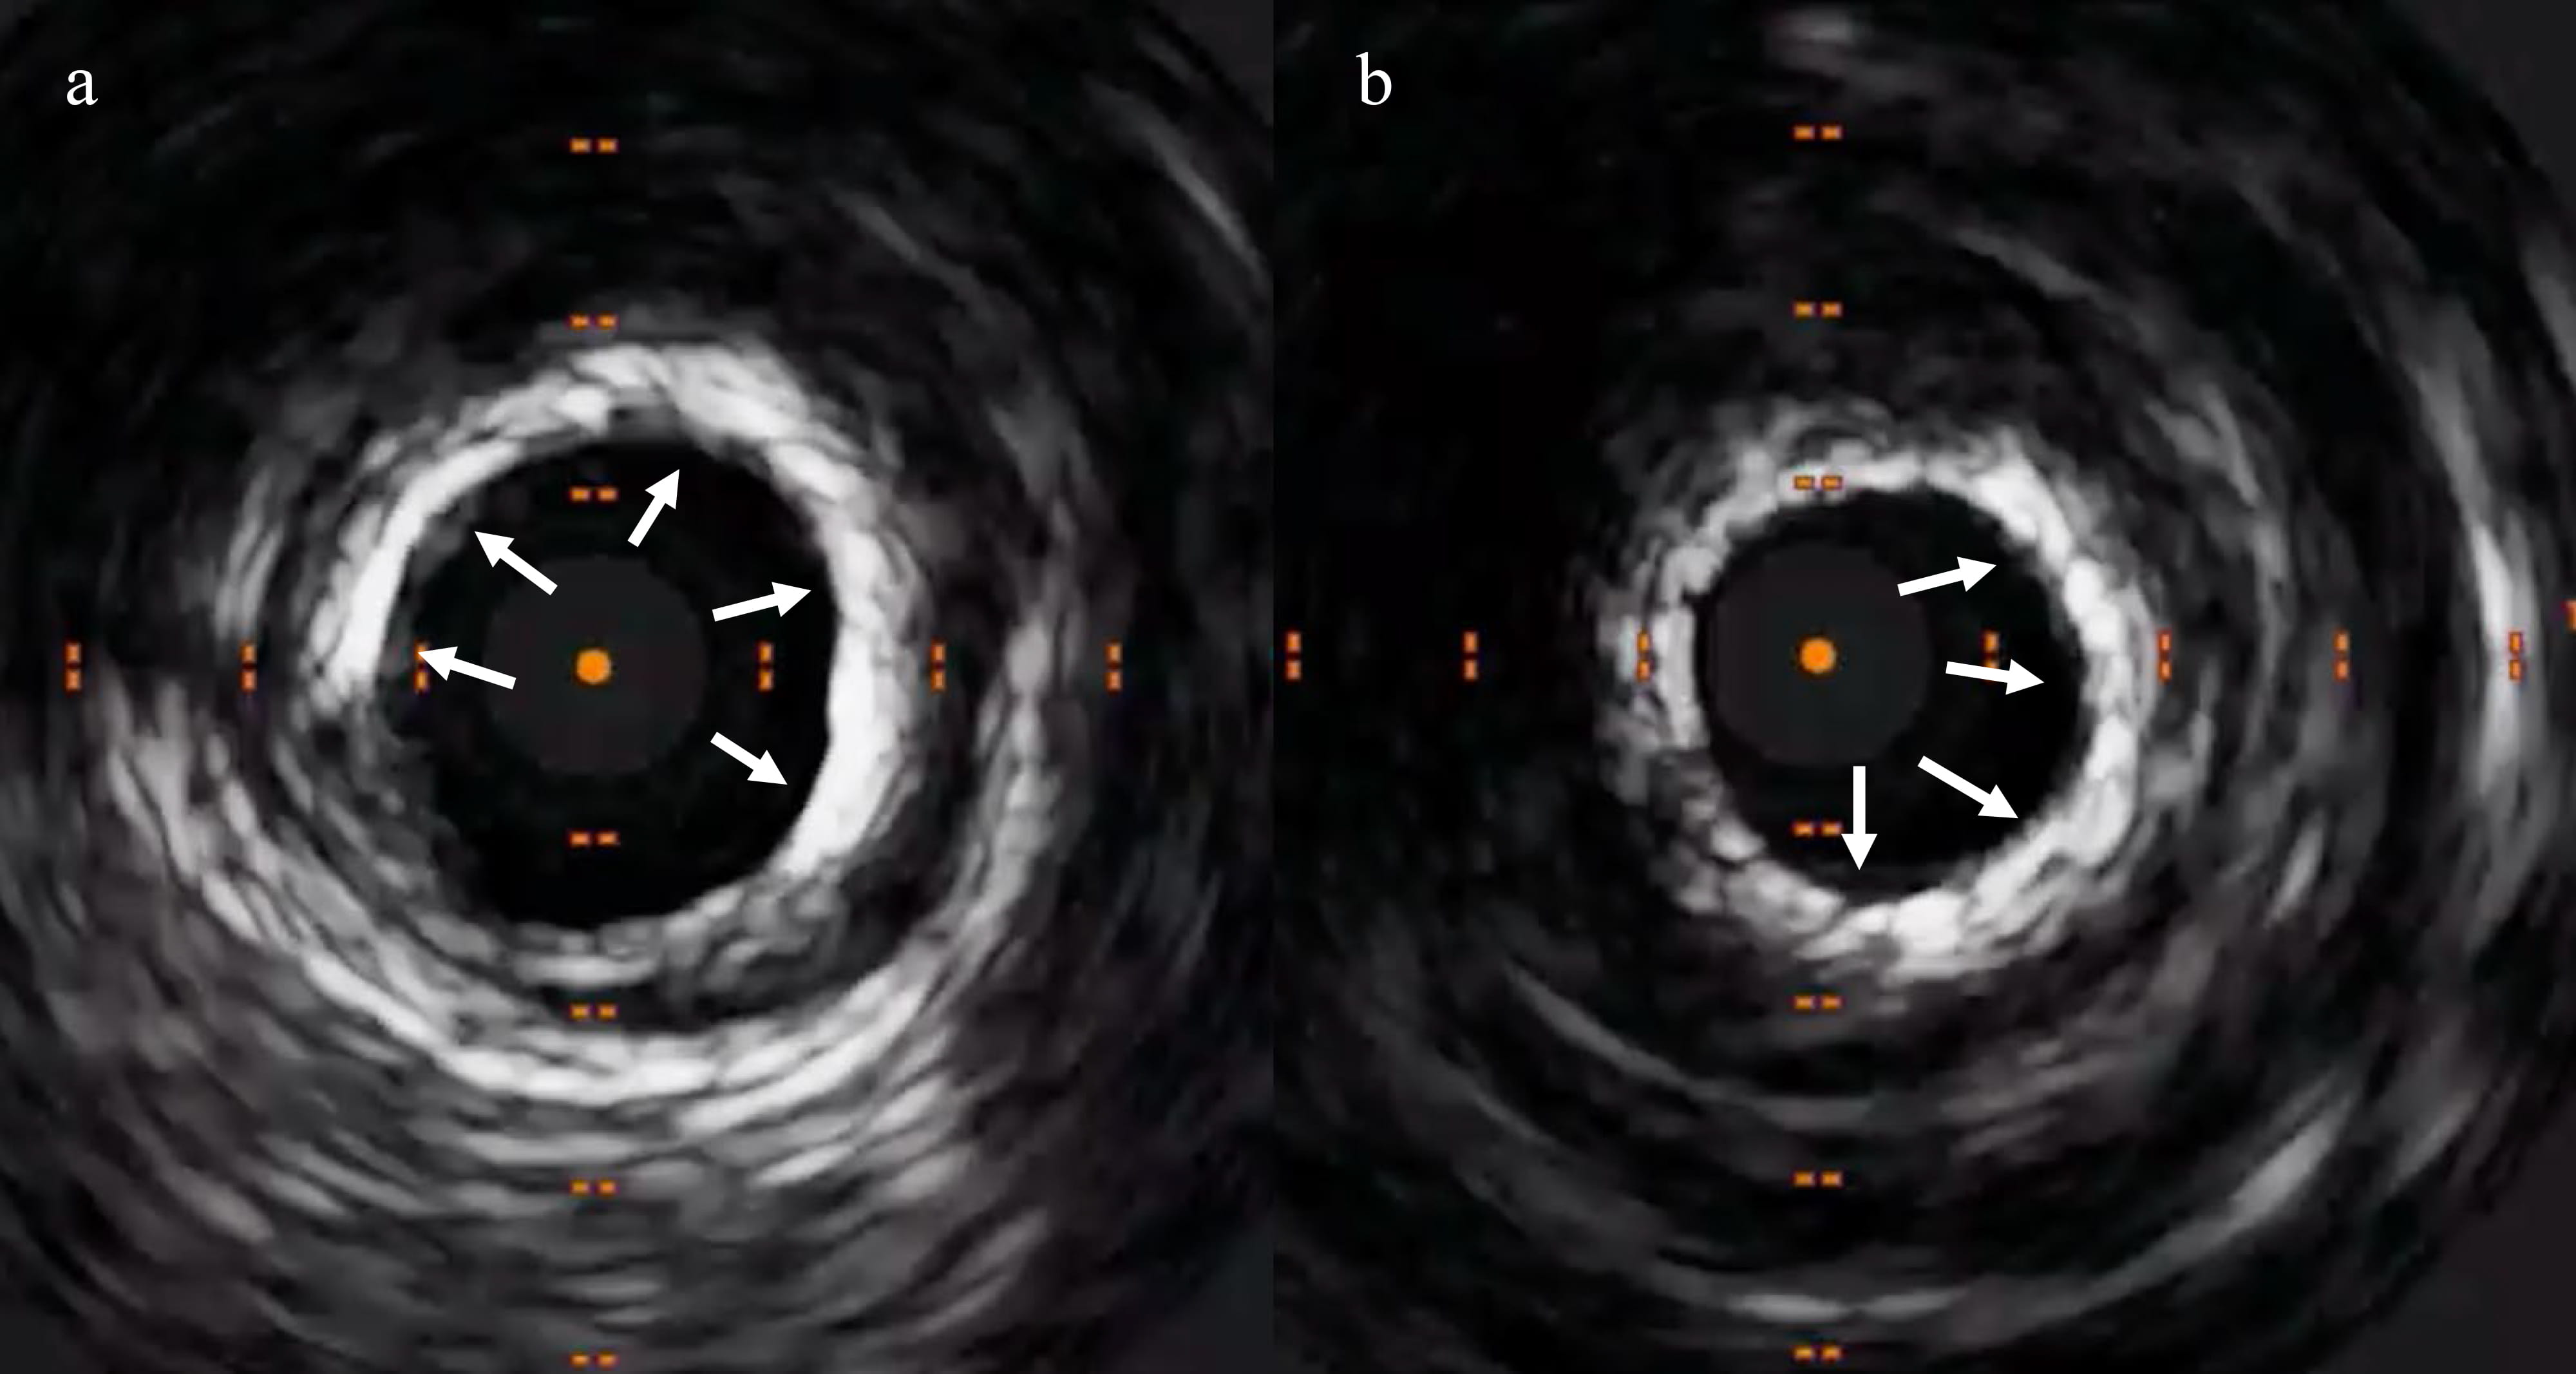

imaging visualised concentric calcium (Fig. 4). Subsequently, we used a 3.5 mm

intra-vascular lithotripsy (IVL) balloon (Fig. 5), which fractured the calcium

Fig. 4.3.5 mm intra-vascular lithotripsy successfully cracked the lesion. (a) 3.5 mm IVL balloon successfully inflated in the mid-segment. (b) IVL balloon expanding in the proximal segment. (c) IVL balloon fully expanded in the proximal segment.

Fig. 5.Repeat IVUS exhibiting crack in the calcium (shown by the arrows). (a) Cracks at 2 and 5’o clock positions. (b) Cracks at 4 and 10’o clock positions. (c) Crack at 1’o clock position. (d) Crack at 3’o clock position (shown by the arrows).